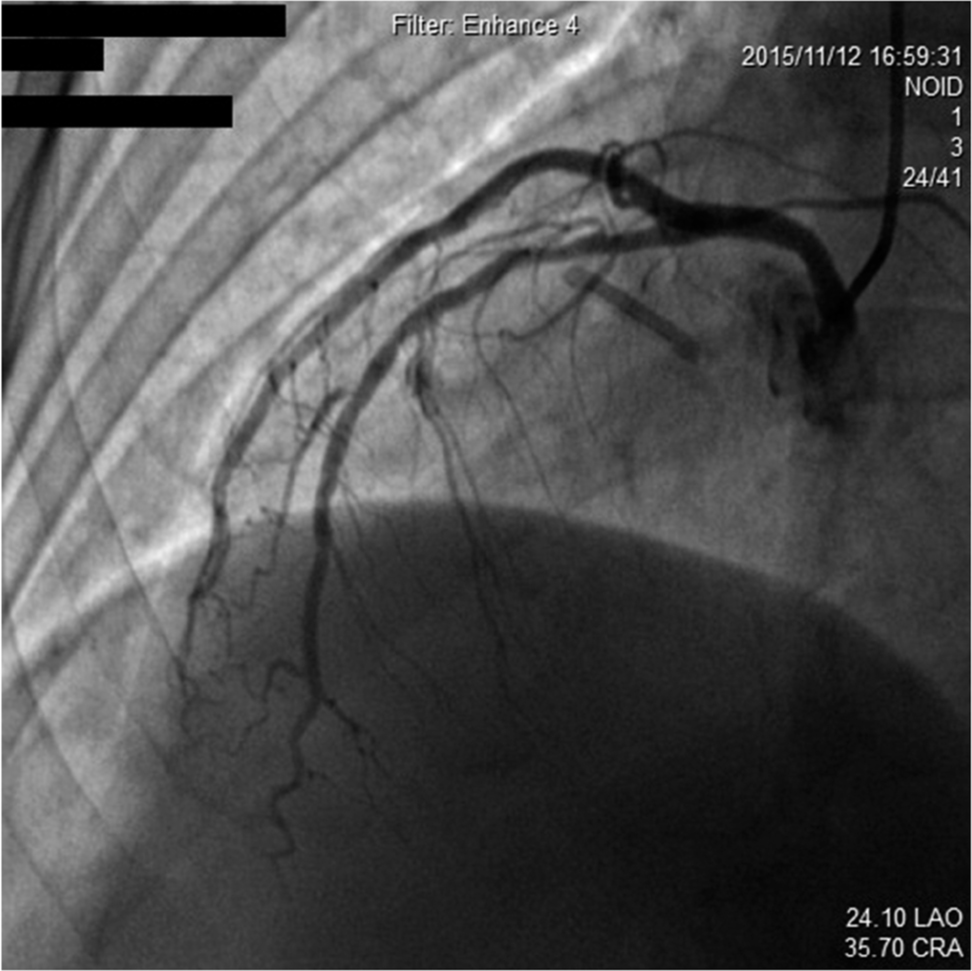

Regarding angiographic findings, no hemodynamically significant stenosis of left anterior descending artery (LAD), left main coronary artery (LM), left circumflex artery (LCX), and antegrade TIMI III flow was found ( Fig. 2). The RCA, as a dominant vessel, was thick with 80% diameter stenosis ( Fig. 3). Assuming this site to be the cause of discomfort, we proceeded with surgical intervention to open the occluded RCA. After balloon pre-dilatation, a Xience V® 3.0 × 23 mm (Abbott Vascular, Santa Clara, CA, USA) drug-eluting stent was subsequently implanted at the lesion site (Fig.4A), using an inflation pressure of 16 atm for 20s. The intervention was successful, achieving optimal antegrade TIMI III flow without residual stenosis (Fig. 4B). The patient’s recovery post-angioplasty was uneventful.

Coronary angiography showing no lesion in LAD.